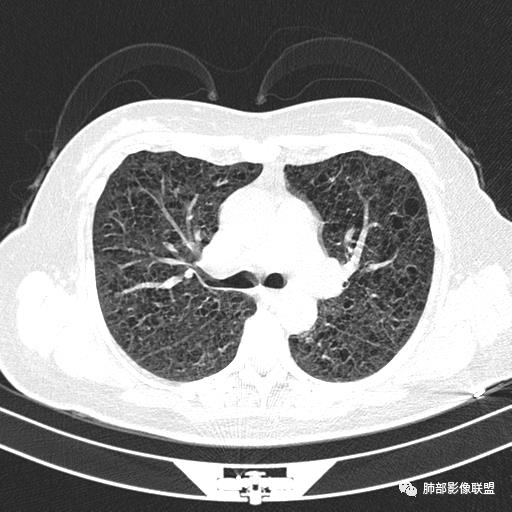

双肺弥漫囊腔,累及肋膈角,囊腔形态相对规则单一。

CT平扫示双肺弥漫分布大小不等囊状薄壁透光区,无内、中、外带分布差异,间质稍示增厚。拟LAM

中年女性育龄期妇女,咳嗽气喘,无吸烟史,有苯吸入史。影像:双肺弥漫均匀小囊腔,无明显分布优势,囊腔形态欠规则,壁薄,部分囊腔边缘血管征,伴双肺弥漫磨玻璃影,无结节,考虑lam,鉴别苯中毒肺损伤,囊腔多有分布优势,小叶中心分布为主,形态规整等

女,46,活动性气喘1年。苯吸入史半年。胸部CT:两肺弥漫囊腔,上至肺尖,下至肋膈角,形态类似小囊腔。考虑:LAM,鉴别LIP,BHD,PLCH等。

CT表现:双肺弥漫大小不等的薄壁囊腔,囊壁<2mm,外形规则,血管影多位于囊腔周围,囊腔之间肺组织正常,随着疾病进展到晚期,囊腔变大、增多,不可胜数,囊腔可融合成较大的囊,与肺气肿相似,形成间质性肺纤维化。部分病例可出现结节影。